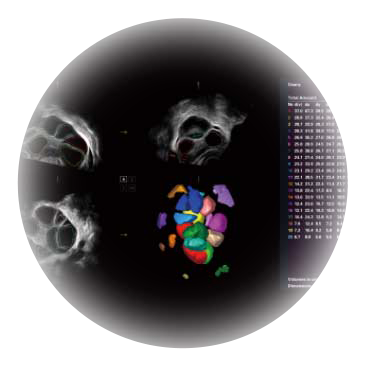

• M-Slice多切面成像

0.5mm厚度的薄层切片显像,可清晰显示微小病灶的连续断面。

• S-Live Silhouette光影成像

可同时显示组织结构表面和内部的轮廓信息,达到透视效果,为临床提供更丰富的诊断信息。